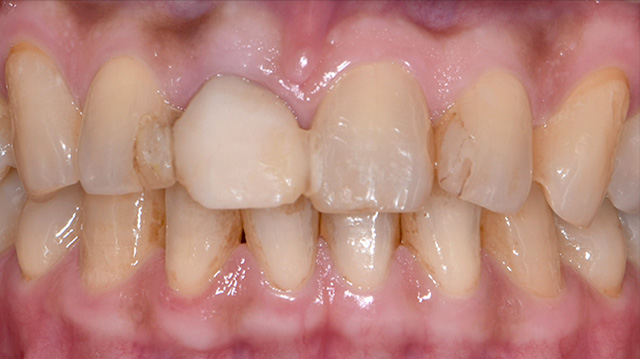

| 年代・性別 | 40代 男性 |

|---|---|

| 主訴 | 前歯の色が気になる |

| 治療回数 | 3回 |

| 治療期間 | 約1ヶ月 |

| 費用 | 仮歯 5,500円 ジルコニアクラウン 176,000円 |